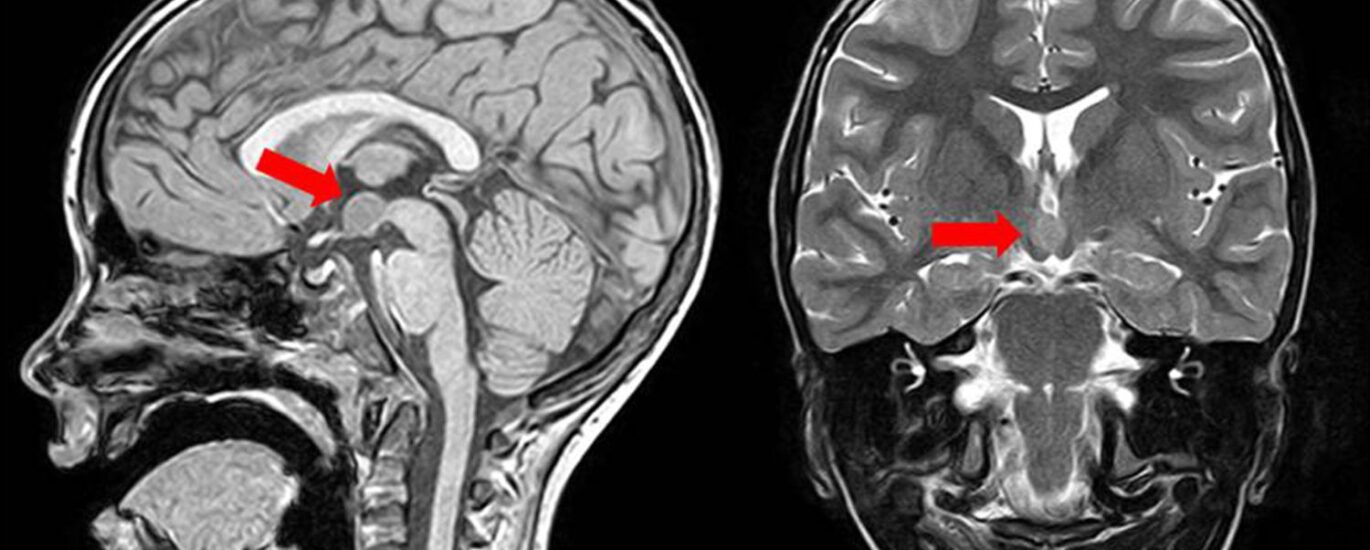

A non-invasive imaging procedure called as perfusion imaging reveals how blood flows through tissues and organs. Perfusion imaging techniques efficiently produce both perfusion measurements and perfusion maps of the area of specific interest. It aids in identifying nutritive blood supply to a crucial component of tissue. The use of these imaging modalities in the perfusion imaging market has increased over time. There are several different perfusion imaging tools on the market. These instruments include computed tomography and microspheres. These imaging technologies help to map the blood flow across the vascular network of the brain.